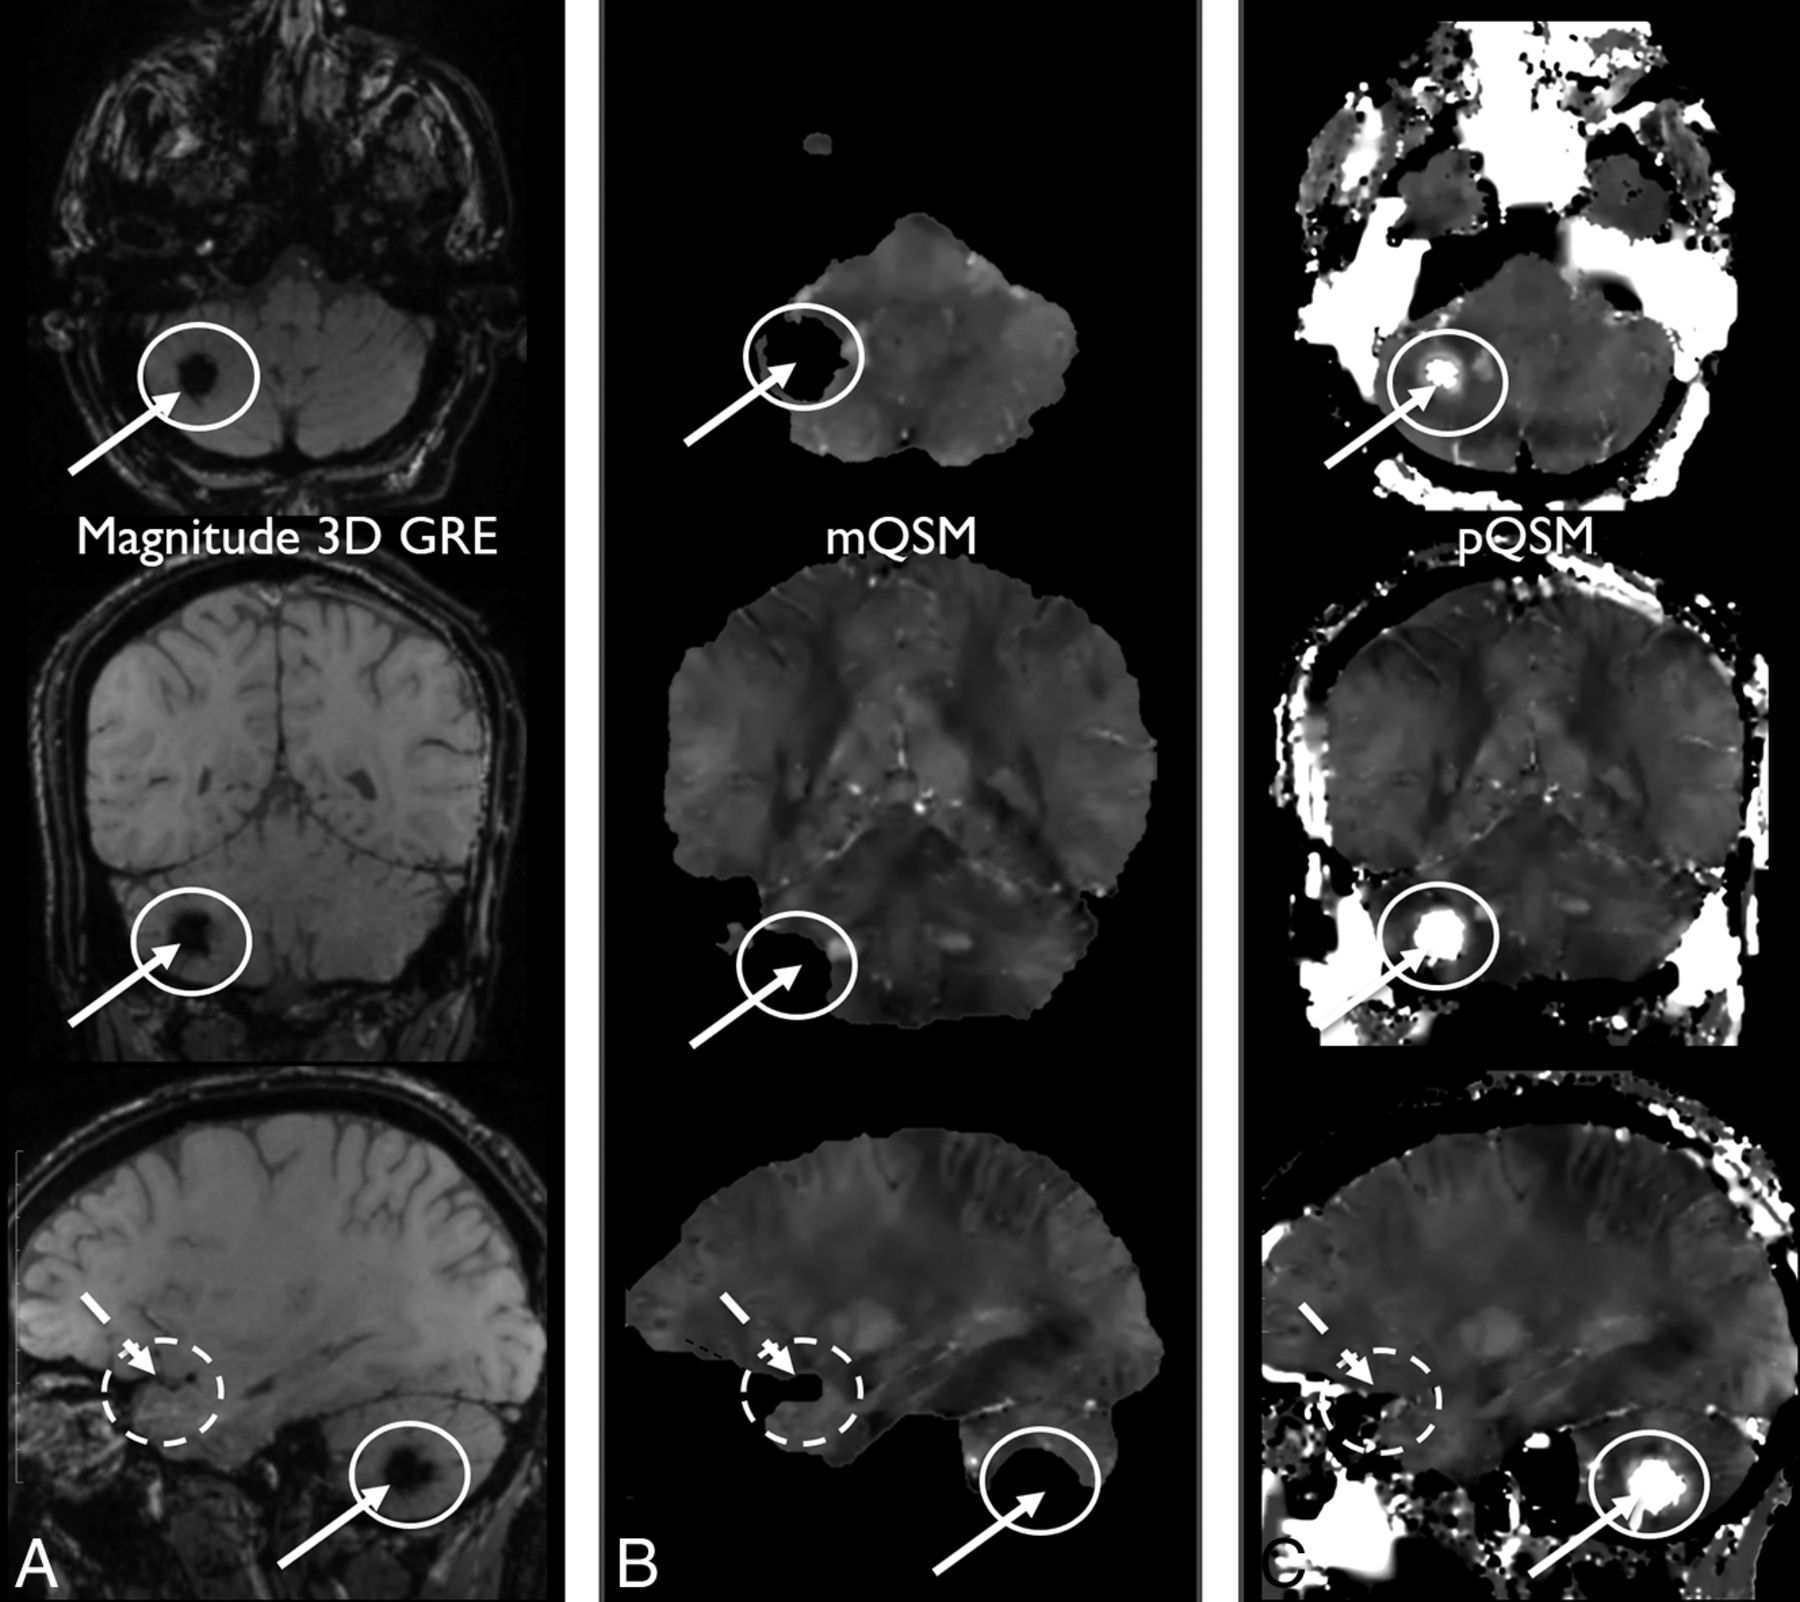

Right cerebellar hemorrhage is hypointense on magnitude 3D GRE (TE = 14.3 ms) (A). This part of the cerebellar parenchyma has been eroded on mQSM (B) and so is not visible due to masking. The same anatomy is preserved on pQSM (C), and hemorrhage is demonstrated (white solid arrows and circles). Additionally, an absent section of the right temporal brain parenchyma on mQSM (B) is partially preserved on the pQSM (C) relative to the 3D GRE image (A) (white dashed arrows and dashed circles). Note areas of black pixels within the white dashed circles on the mQSM and pQSM images (B and C) that correspond to brain tissue seen on 3D GRE image (A) indicate areas of nonvisualized brain.

Of the 10 subjects with blood on a 3D GRE image, these cases had pQSM images depicting those lesions, but only 4 of these lesions were visible on the mQSM images, due to nonvisualized brain parenchyma, which was a statistically significant difference (P < .01).

Thirty-one subjects (55%) demonstrated brain parenchyma (some containing lesions) preserved on pQSM but eroded on mQSM due to masking. Five subjects (9%) demonstrated areas of more nonvisualized brain parenchyma on mQSM compared with that same region on pQSM images (P = .88, Table 1 and Fig 3). In subjects in whom there was brain parenchyma nonvisualization on mQSM or pQSM, none demonstrated greater areas of nonvisualized brain parenchyma on pQSM relative to mQSM images. Overall, there was more brain parenchyma visualization on pQSM images compared with corresponding mQSM images. The differences in parenchymal depiction on pQSM compared with mQSM were statistically significant (P < .01). There was not a statistically significant difference in age (P = .76), sex (χ2 = 0.04, P = .84), TBI severity (χ2 = 2.20, P = .5, Table 1), or the presence of blood products on 3D GRE (χ2 = 2.99, P = .08, Table 1) for cases demonstrating nonvisualized brain parenchyma on mQSM relative to cases that did not. Six subjects (11%) demonstrated mQSM and pQSM pons hypointensity with no corresponding 3D GRE finding suggestive of artifacts, all larger on pQSM than on corresponding mQSM images (Fig 4).

This report shows that pQSM can depict more brain parenchyma than masked-based QSM using the same acquisition data. Comparing these images generated from a single multiecho 3D GRE scan allowed evaluation of imaging features while holding other acquisition parameters constant (eg, field strength, flip angle, sampled TEs, and so forth.). Additionally, our results demonstrate that some of these areas of brain visible on pQSM but not present on mQSM contained clinically relevant pathology, such as CMHs. This difference in brain depiction is consistent with the expectation that variations in skull-stripping performance and variations of intensity that threshold-based masking algorithms use, especially near hemorrhages (as demonstrated in Figs 2 and 3), can result in areas of nonvisualized brain on mQSM methods. This contrasts with pQSM, which uses magnitude information to differentiate weak from strong sources of susceptibility over the entire head for reconstruction. Instead of splitting the QSM problem into background field removal and local field fitting (in which errors are propagated from the first into the second), preconditioned QSM solves them together. Demonstration of better preservation of brain parenchyma in pQSM compared with mQSM in subjects was independent of age, sex, and the presence of hemorrhage or history of prior trauma; this finding suggests generalizability across patients. The preservation of anatomic landmarks, such as skull margins, on pQSM images also has the potential to aid in clinical interpretation. The feature of preserving skull and scalp in pQSM may also allow better depiction of calvarial and skin masses if challenges regarding scalp SNR and implementation of a robust water/fat separation algorithm can be managed.